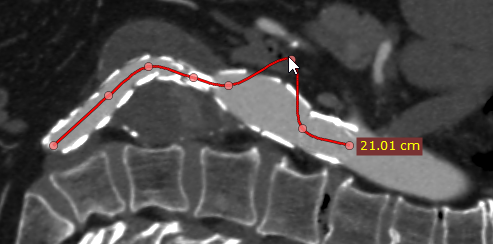

编辑开放多边形

要移动已有节点,将光标悬停在节点上方,按住鼠标左键将节点拖动到目标位置后松开。

编辑节点